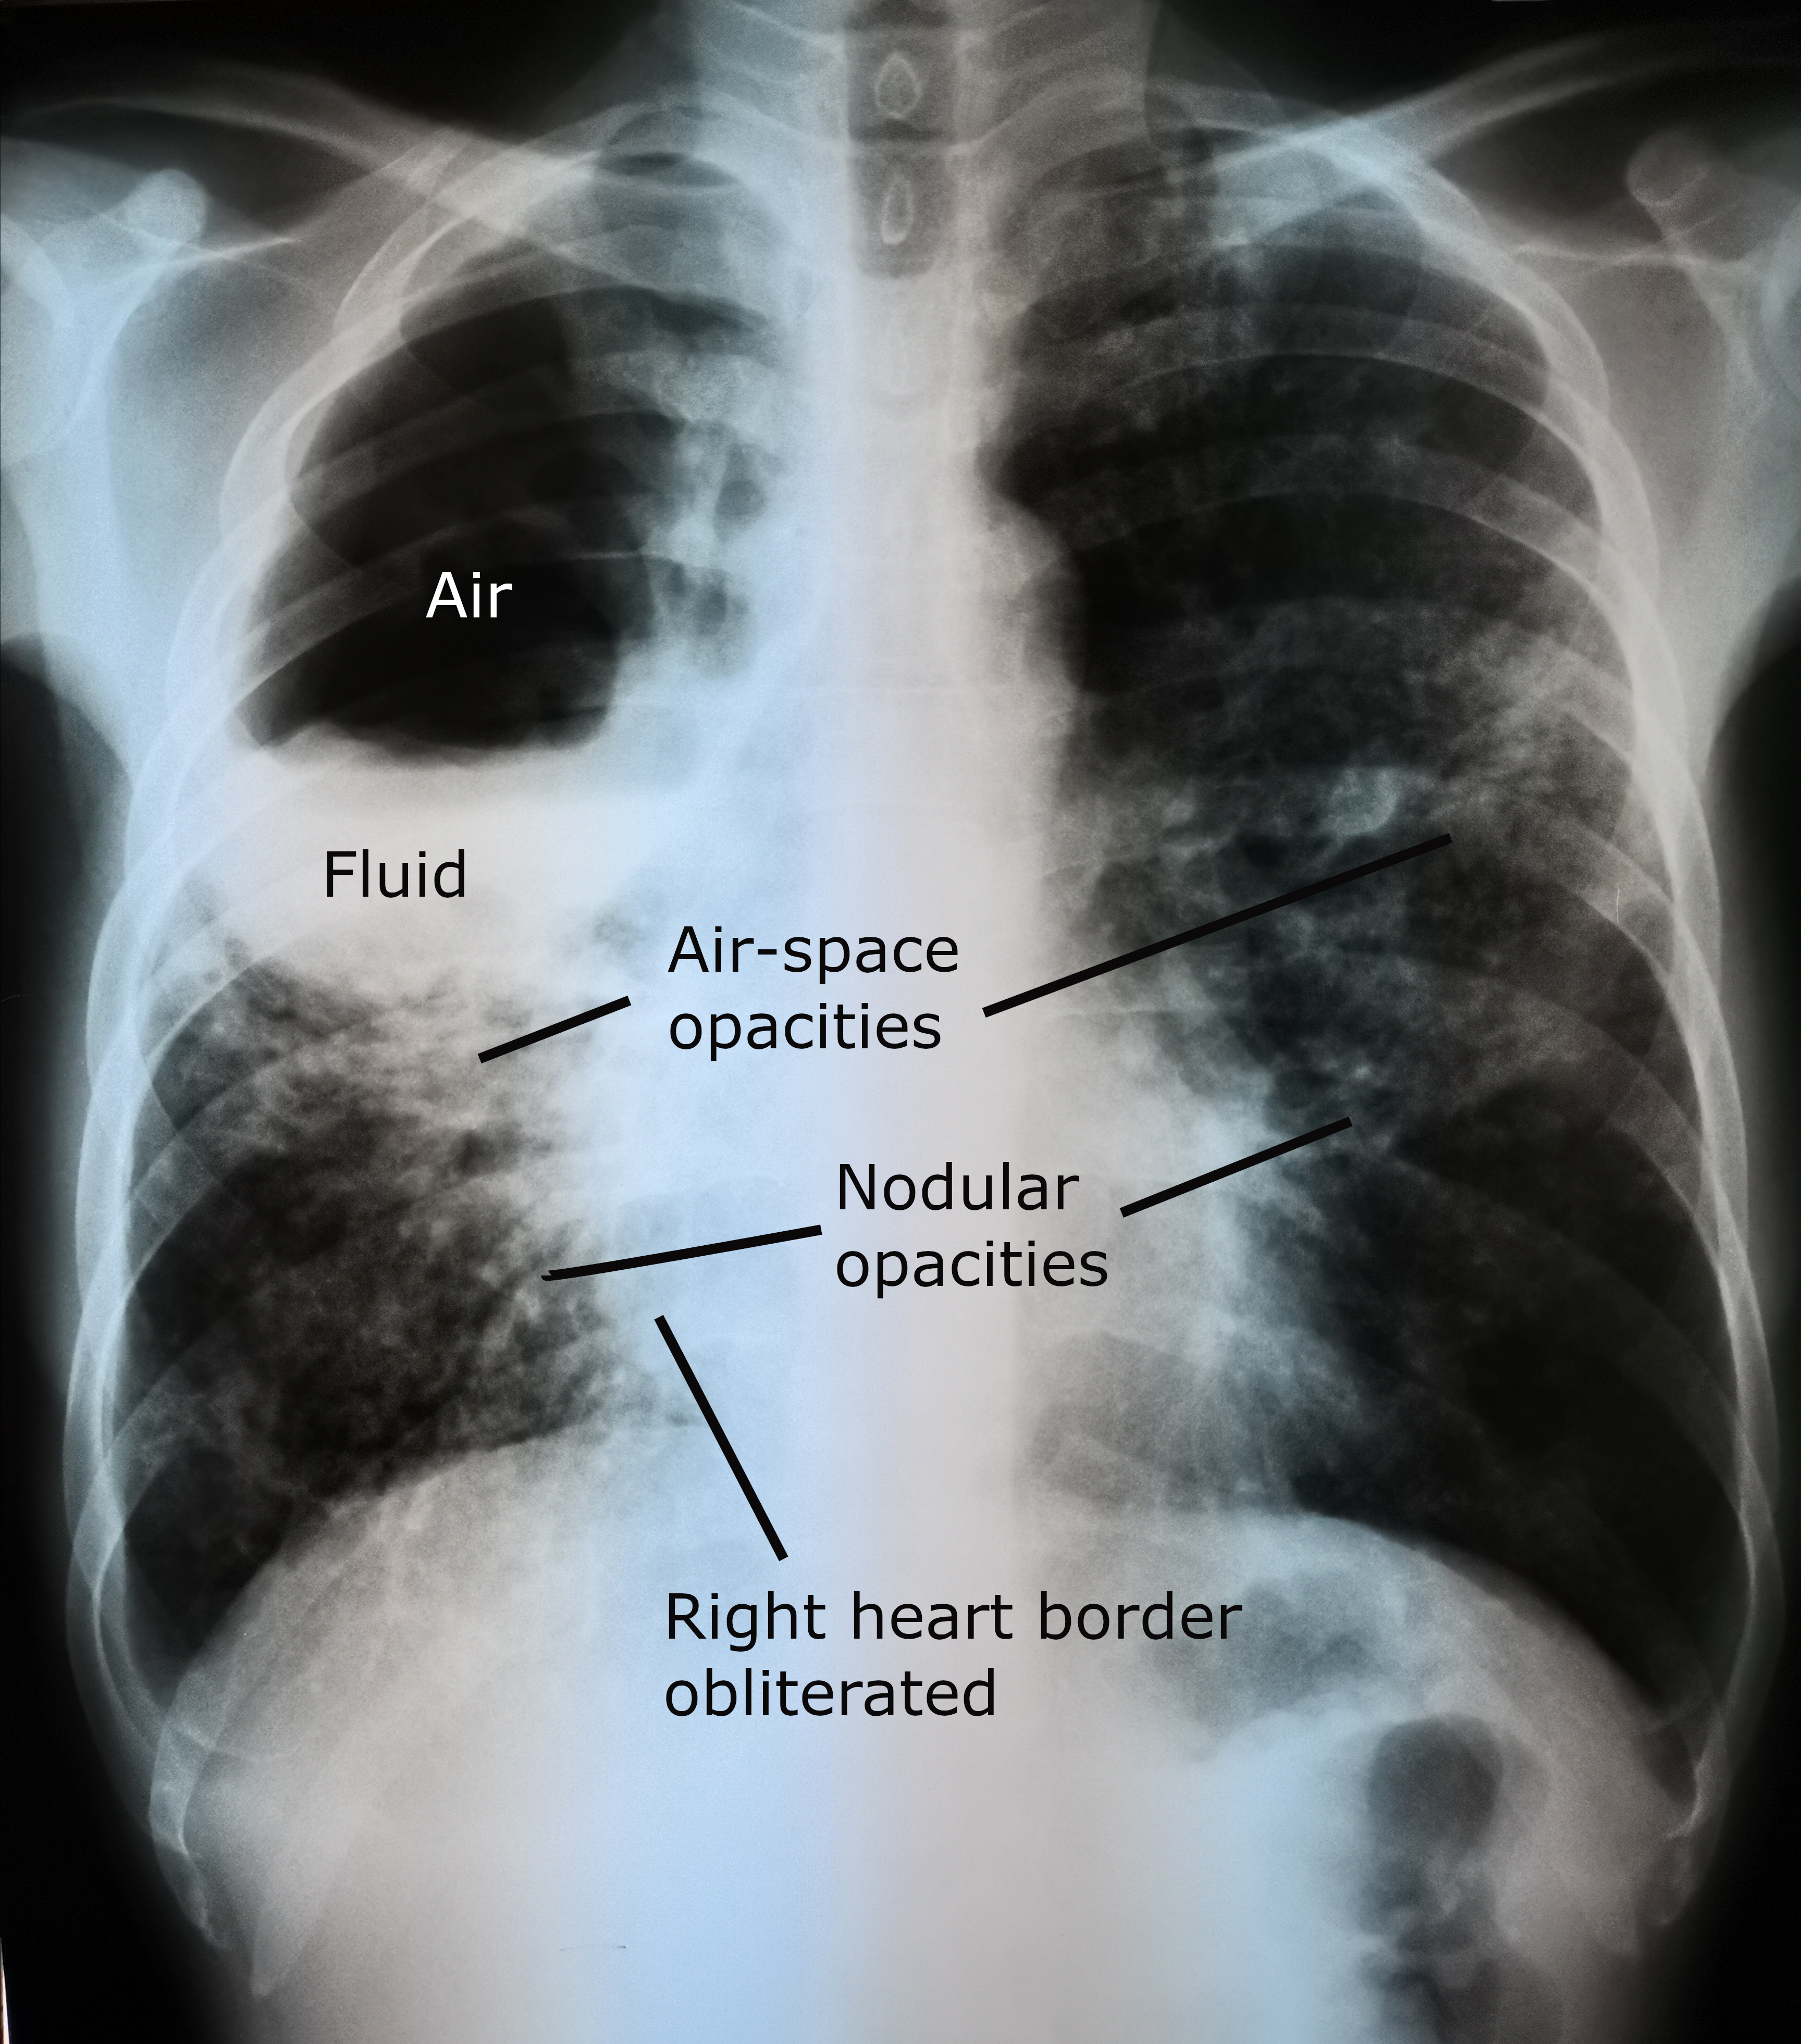

- Chest X-ray: consolidation early; classic rounded cavity with air-fluid level when communication with bronchial tree established

- CT thorax: characterises the abscess, identifies associated pathology, guides drainage